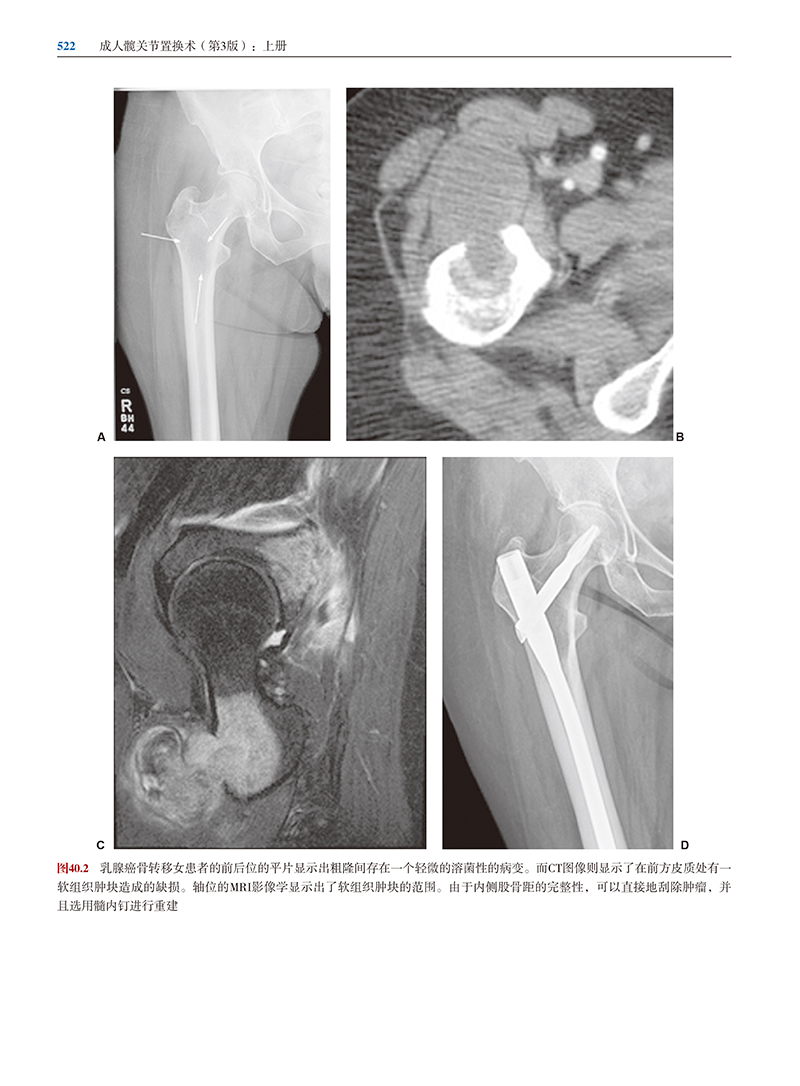

本书由世界著名的髋关节置换手术大师编写,本书为上册和下册,主要讲解了新的技术的操作和应用。专家们分享的临床经验使从手术中不断完善来的,包括基础科学、临床医学、全髋关节置换术、全髋关节翻修术,对于并发症,本书更有详细而且实用的介绍。